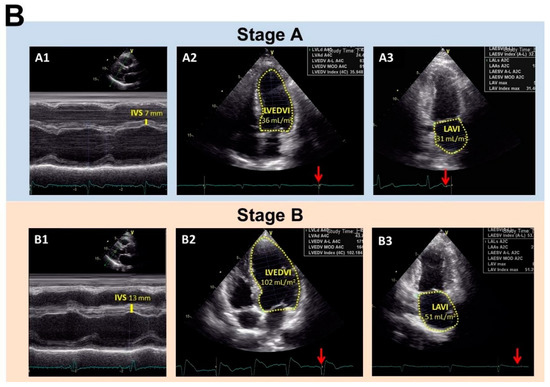

2.5. Definition of Stages A and Stage B Heart Failure

| Left atrial volume index (mL/m2) | 34.61 ± 9.62 | 42.92 ± 12.32 | <0.001 |

| Left ventricle EDVI 2 (mL/m2) | 54.22 ± 12.21 | 62.39 ± 19.79 | 0.009 |

| Left ventricle mass index (g/m2) | 75.76 ± 17.56 | 104.45 ± 28.73 | <0.001 |